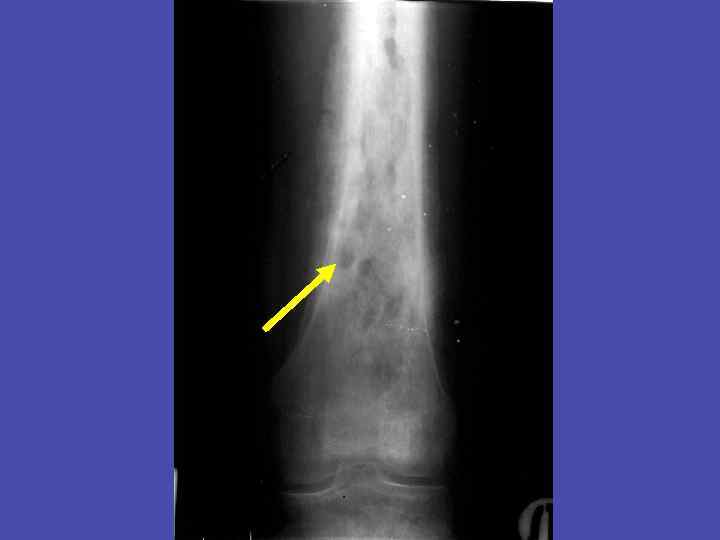

Линейный периостит, деструкция метадиафиза, перфорационные отверстия большеберцовой кости 34

Периостит, деструкция метадиафиза, перфорационные отверстия плечевой кости 35